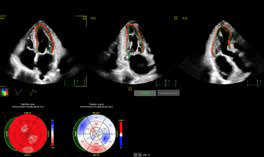

Desde inicios de 2024, Punta del Este recibió al cardiólogo argentino Martín Lombardero, pionero en imagen cardíaca en América Latina. Con el avanzado ultrasonido cardiovascular PHILIPS EPIQ CVx, que integra inteligencia artificial y tecnología 3D, revolucionó los diagnósticos cardíacos, permitiendo prevenir enfermedades de forma inédita. En su libro “El corazón es consciente: Puedes cambiar tu destino cardiológico”, con una narrativa que nos remite al realismo mágico, nos presenta casos médicos en los cuales intervino que nos revelan cómo las emociones pueden sanar o enfermar. Para él, entender el corazón es un viaje profundo hacia el alma y una invitación a escuchar lo que realmente sentimos.

El Dr. Martin Lombardero estará atendiendo (estudios e interconsultas) en la Clínica Blue Cross & Blue Shield Uruguay de Punta del Este.